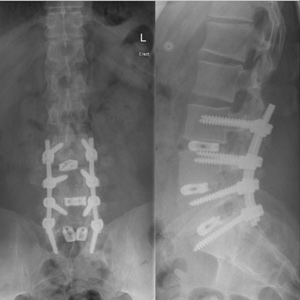

Spinal stenosis (Lumbar) Spinal stenosis (Cervical) Spinal stenosis (Thoracic) Lumbar Disc Herniation Spondylolisthesis Cervical Foraminal Stenosis Vertebroplasty Lumbar Fusion Anterior Cervical Fusion (ACDF) Posterior Cervical Fusion Thoracic Fusion Revision Lumbar Fusion Surgery Facet Joint Cyst Spinal Tumour Minimally Invasive Lumbar Fusion (XLIF) Minimally Invasive Lumbar Fusion (ALIF) Lumbar Fusion (TLIF) Thoraco-lumbar Fusion Lumbar Corpectomy Complex Lumbar Spine Surgery (Spino-pelvic fixation) Complex Cervical Spine Surgery Complex Thoracic Spine Surgery Occipito-cervical Fusion Minimally invasive surgery for thoracic disc herniation Other Related Topics